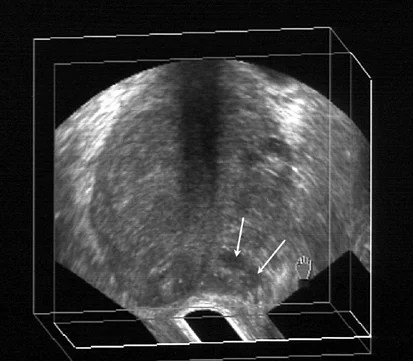

Being armed with information is vital to begin the fight. Transrectal ultrasound and prostate biopsy (TRUS Biopsy

Transrectal ultrasound and prostate biopsy (TRUS Biopsy from static1.squarespace.com